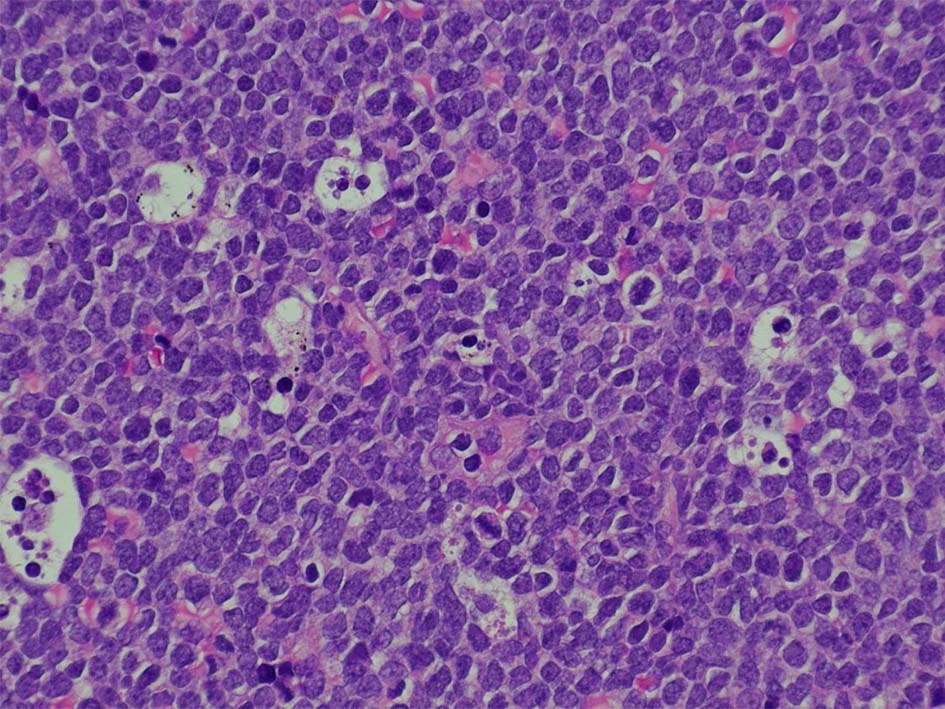

右肺上葉から前縦隔に90mm大の腫瘤あり. 右胸水貯留を伴う. 右主気管支より縦隔腫瘍のEBUS-TBNAをおこなう.

断片状組織片が採取され, 小型から中型の円形細胞がシート状密に増殖する. tindible body macrophagesが散在しstarry-sky様組織像を呈する組織片がある. CD3+, CD5+, CD20-, Ki-67 LI veru high(>95%),CD10-, BCL2(淡染だがほぼ100%膜陽性), BCL6陽性, MYC+(69%). T-cell neoplasmであるが, double expressorである. EBER-ISH陰性. CD4, CD8 double positive cellの増殖. CD25-, TIA1, granzymeBはいずれも陰性.